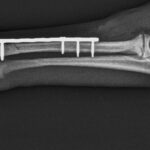

¿Cuánto cuesta un tratamiento veterinario para fracturas de huesos en caballos?

El costo de un tratamiento veterinario para fracturas de huesos en caballos puede variar dependiendo del tipo y gravedad de la lesión, así como de la región geográfica. Es recomendable contactar a un veterinario especializado para obtener una cotización precisa.

¿Cuál es la duración promedio de una cirugía para corregir fracturas óseas en caballos?

La duración promedio de una cirugía para corregir fracturas óseas en caballos puede variar dependiendo del tipo y gravedad de la fractura, pero generalmente puede durar entre 2 a 4 horas.